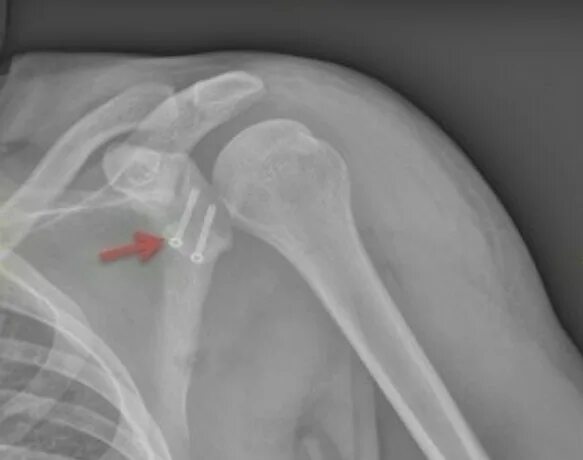

Нестабильность плечевого сустава мкб